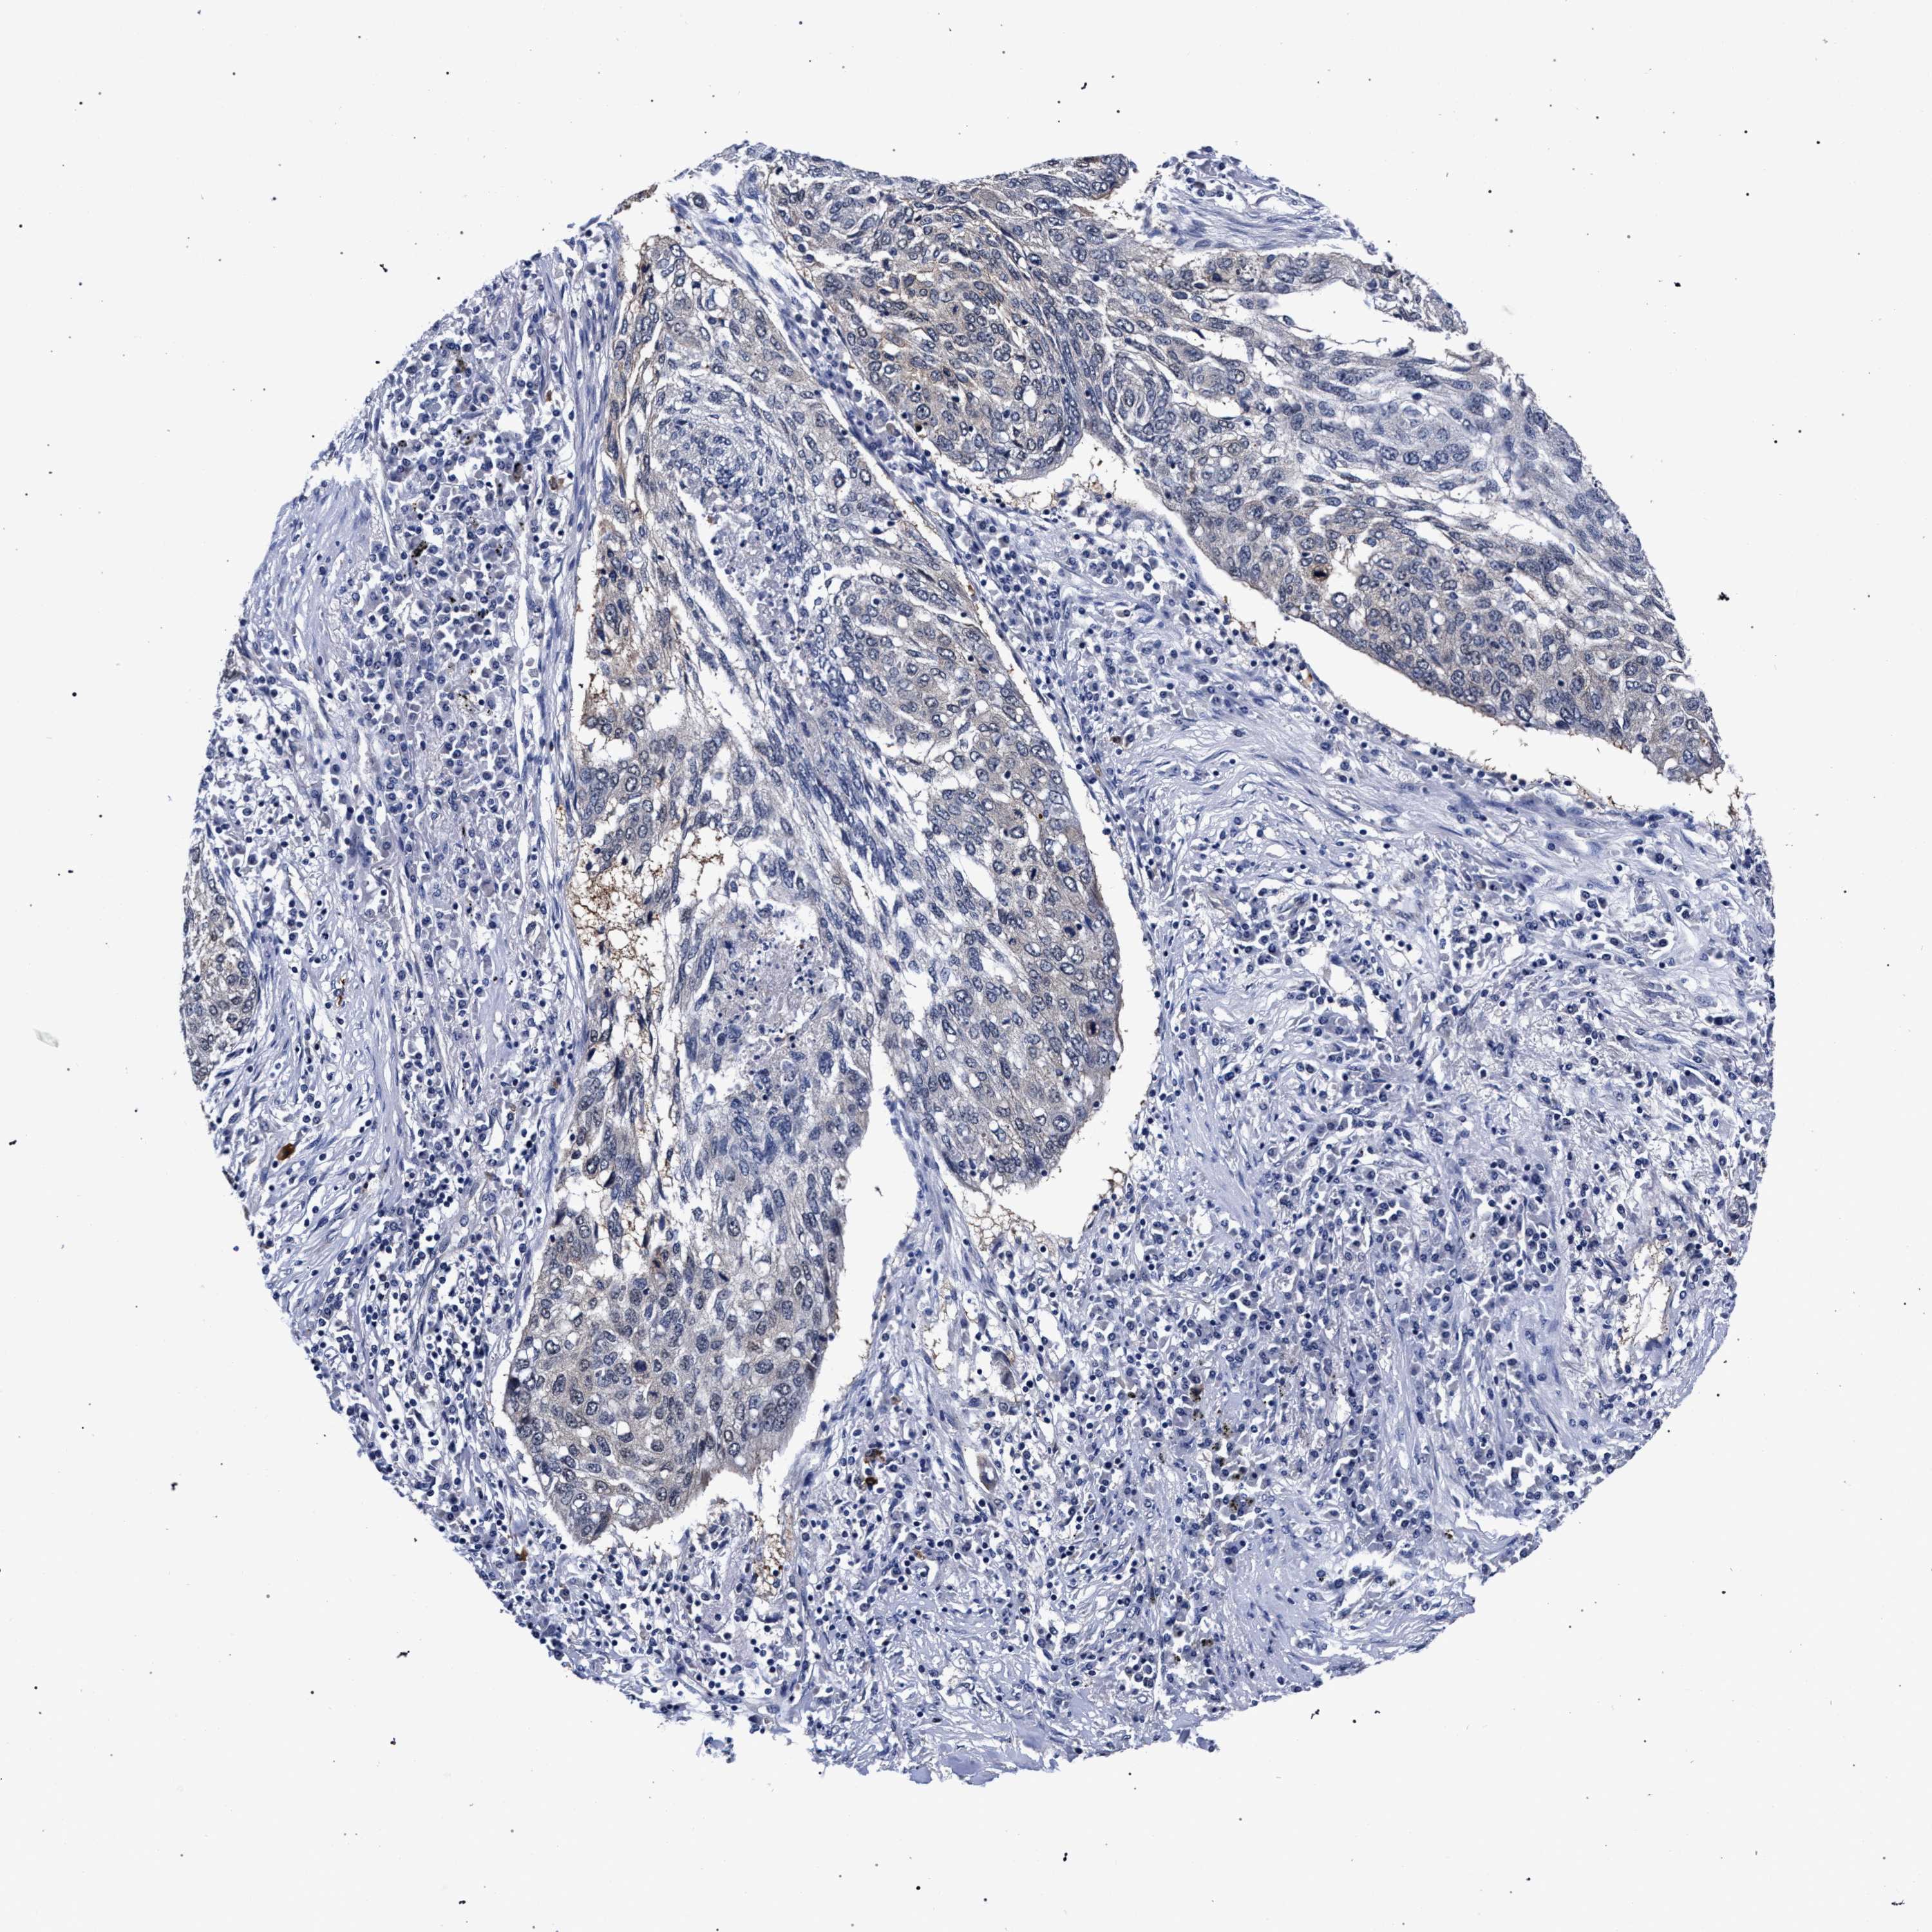

LUNG ADENOCARCINOMA (TCGA) - Interactive survival scatter ploti

The Survival Scatter plot shows the clinical status (i.e. dead or alive) for all individuals in the patient cohort, based on the same data that underlies the corresponding Kaplan-Meier plots. Patients that are alive at last time for follow-up are shown in blue and patients who have died during the study are shown in red.

The x-axis shows the expression levels (FPKM) of the investigated gene in the tumor tissue at the time of diagnosis. The y-axis shows the follow-up time after diagnosis (years). Both axes are complimented with kernel density curves demonstrating the data density over the axes. The top density plot shows the expression levels (FPKM) distribution among dead (red) and alive patients (blue). The right density plot shows the data density of the survived years of dead patients with high and low expression levels respectively, stratified using the cutoff indicated by the vertical dashed line through the Survival Scatter plot. This cutoff is automatically defined based on the FPKM cutoff that minimizes the p-score. The cutoff can be changed by dragging the vertical line or by entering a cutoff value in the square labeled "Current cut-off".

Under the Survival Scatter plot the p-score landscape (black curve; left axis) is shown together with dead median separation (red curve; right axis). Dead median separation is the difference in median mRNA expression between patients who have died with high and low expression, respectively. It is calculated as follows: median FPKM expression of dead patients with high expression - median FPKM expression of dead patients with low expression. This is intended to aid the user in visually exploring custom cutoffs and the associated p-scores and dead median separation.

Individual patient data is displayed and can be filtered by clicking on one or more of the category buttons on the top of the page. Categories describing expression level and patient information include: high, low, alive, dead, female, male and tumor stages. The scale of the x-axis can be toggled between linear and log-scale by clicking on the "x log" button. Mouse-over function shows TCGA ID, patient information and mRNA expression (FPKM) for each patient.

& Survival analysisi

Kaplan-Meier plots summarize results from analysis of correlation between mRNA expression level and patient survival. Patients were divided based on level of expression into one of the two groups "low" (under cut off) or "high" (over cut off). X-axis shows time for survival (years) and y-axis shows the probability of survival, where 1.0 corresponds to 100 percent.

RBM33 is not prognostic in Lung Adenocarcinoma (TCGA)

: 10.7